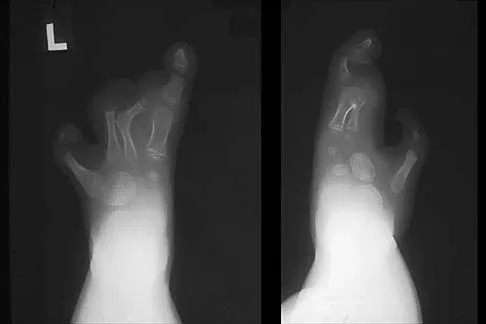

The inheritance of the deformity shown in Figure 1 is most commonly

Correct Answer: autosomal-dominant.

Cleft hand and cleft foot malformations are commonly inherited as autosomal-dominant traits and are associated with a number of syndromes. An autosomal-recessive and an x-linked inheritance pattern have also been described, but these are much less common and are usually atypical. In the common autosomal-dominant condition, nearly one third of the known carriers of the gene show no hand or foot abnormalities. This is known as reduced penetrance. The disorder may be variably expressed; affected family members often exhibit a range from mild abnormalities in one limb only to severe anomalies in four limbs. Variable expressivity and reduced penetrance can cause difficulty in counseling families regarding future offspring in an affected family. Many patients have a cleft hand that may be caused by the split-hand, split-foot gene (SHFM1) localized on chromosome 7q21.